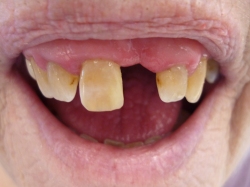

Partiel protese

Den partielle protese bliver ofte kaldt en overgangsprotese, da den er mulig at udvide med flere tænder. Derfor bruges den også oftest, hvis dine egne tænder er svage eller ikke forventes at have så lang levetid. Denne type protese ligger på gummen og kan derfor være mere ustabil i sammenligning med en unitorprotese. Samtidig fylder den mere i munden og har en lavere holdbarhed.